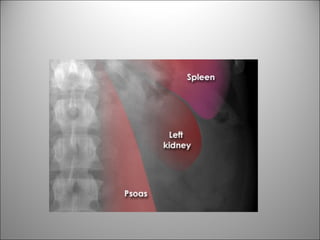

TEJIDO BLANDO

• Visión limitada de estructuras-órganos

• Puede verse +/-

– Hígado

– Bazo

– Riñones

– Psoas

– Vejiga

– Bases pulmonares